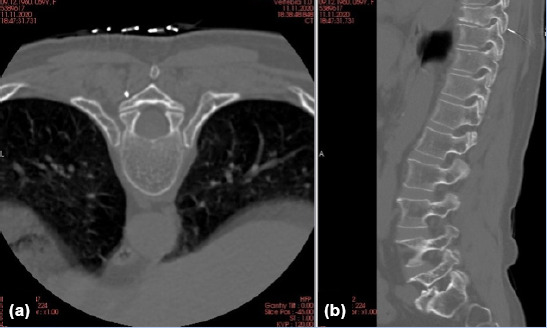

Methods: Fourteen patients undergoing posterior aproach to the thoracic spine and/or spinal cord related lesions were investigated. Spinocaths were placed under CT guidance, into the pedicle of the relevant vertebra, at the same day or the night before surgery. The surgical field is prepared as usual, and a spinocath is placed to the relevant thoracic pedicle under CT guidance.

Results: Intraoperative level localization was more reliable and easier in patients undergoing preoperative CT-guided marking in surgeries on the thoracic region performed for various reasons. Shorter preoperative preparation and intraoperative anesthesia times, a decrease in number of fluoroscopic images taken intraoperatively, and no spinal mislocalizations were observed.